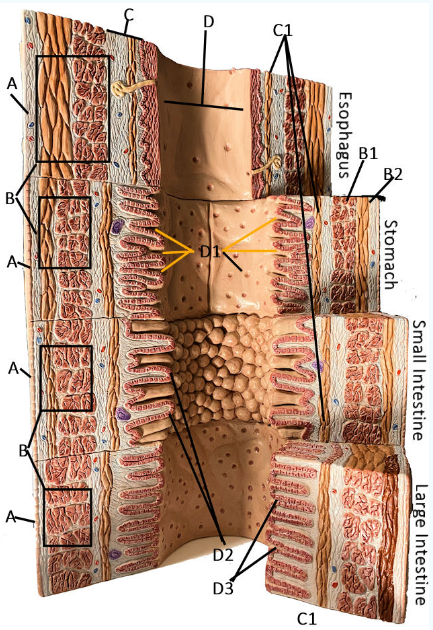

A

Serosa

B Esophagus

Muscularis externa: skeletal, skeletal/smooth, and smooth, circular and longitudinal

B Stomach

Oblique, circular, and longitudinal smooth muscle

B Small intestine

circular and longitudinal smooth muscle

B large intestine

circular and longitudinal smooth muscle

C

Submucosa: areolar and dense connective tissue

D

Lumen

D1

Gastric glands/pits

D2

Villi of small intestine

D3

Intestinal crypts of large intestine